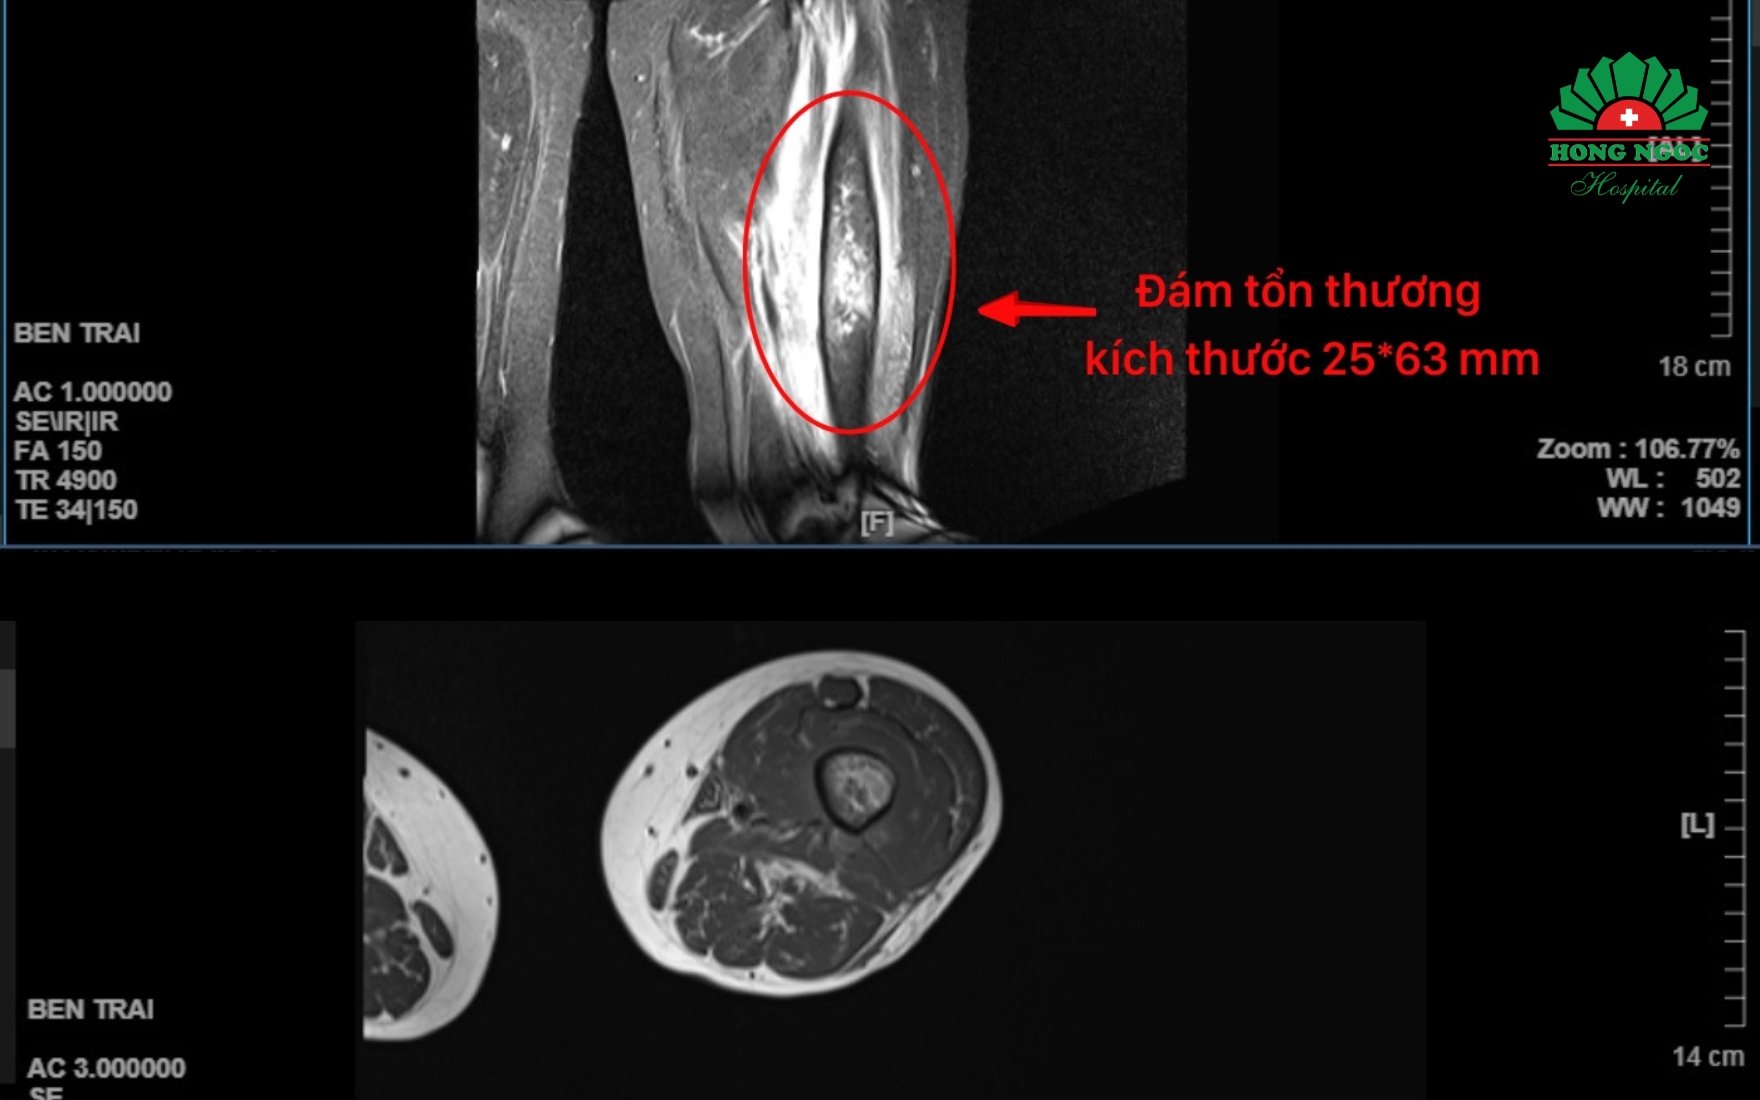

Đúng như dự đoán, kết quả xét nghiệm máu của bệnh nhân Hồng cho thấy bạch cầu tăng, định lượng CRP (đo mức độ viêm trong cơ thể) tăng mạnh, cao gấp hơn 41 lần mức cho phép. Cùng với đó, trên ảnh chụp MRI, ở vị trí 1/2 dưới xương đùi có đám tổn thương kích thước 25*63mm tăng tín hiệu bất thường, hướng đến tổn thương viêm xương tủy. Trong cơ đùi trước và sau có các ổ tín hiệu bất thường kích thước khoảng 10mm, hướng đến tổn thương áp xe trong cơ đùi. Các bác sĩ xác định bệnh nhân bị viêm xương tủy vị trí 1/2 dưới xương đùi trái, áp xe cơ đùi trái.

Ảnh chụp MRI vùng đùi trái của bệnh nhân P.T. Hồng